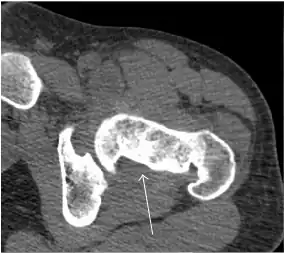

Computed Tomography

Due to radiation concerns, CT has been relegated after MRI in the study of intra-articular causes of hip pain. The only exception where CT is considered superior to MRI is in bone tumors, because of its ability in characterizing matrix calcifications, and in depicting the anatomy of acute traumatic fractures. Typical matrix calcifications include the following: (a) osteoid mineralization, like a dense cloud, (b) chondroid calcification, reproducing a punctate popcorn pattern, or (c) fibrous calcification, ground glass-like appearance. There are also tumors that typically do not show matrix calcification. CT is also used for accurate localization of the nidus in osteoid osteomas and this must be differentiated from Brodie’s abscess or a stress fracture. The current standard treatment of osteoid osteoma is percutaneous radiofrequency ablation and this is usually performed under CT guidance.[1]

Quite often, CT is widely available unlike MRI, especially in the acute setting. CT is performed in this setting when doubt about the existence of a fracture persists following plain radiograph. Modern multidetector computed tomography (MDCT) shows results comparable with MRI for detecting occult fractures.[1]

Due to the submillimeter resolution of MDCT arthrography, many authors consider this technique complementary to MR arthrography. It may even have superior sensitivity in detecting cartilage pathology, but lesser detecting labral tears.[1]

Synovial chondromatosis can be confidently diagnosed by X-ray when calcified cartilaginous chondromas are seen. However, other synovial proliferative processes, such as pigmented villonodular synovitis, require MRI for accurate diagnosis, although noncalcified synovitis can be suspected in radiographs by indirect signs, such as soft tissue swelling and/or erosions in the femoral head, femoral neck, or acetabulum (Figure 7).[1]

Figure 7:

-

Axial CT image of pigmented villonodular synovitis eroding the posterior cortex of the femoral neck.[1] -

Sagittal T2* gradient echo image showing a posterior soft tissue mass with hypointense areas secondary to hemosiderin deposition.[1] -

X-ray of synovial chondromatosis.[1] -

CT of synovial chondromatosis.[1]